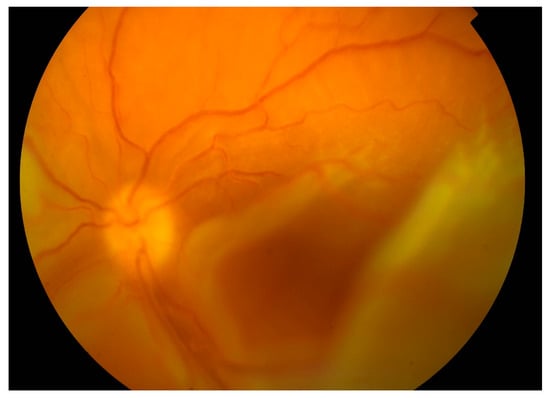

From 2015 to 2017, the patient’s BCVA undulated from 20/200 to counting fingers on both eyes. Intravenous corticosteroid pulses were administered when vision worsened. Retinal detachments were still present with periodic enlargements of the subretinal fluid. In 2017 visual acuity worsened bilaterally despite corticosteroid pulses (BCVA oculus dexter (OD): counting fingers, oculus sinister (OS): hand movement). Retinal detachment enlarged. In the left eye, bullous retinal detachment developed with involvement of the macula (Figure 4).

Figure 4. Color fundus photography of the detached retina with macular involvement on the left eye.